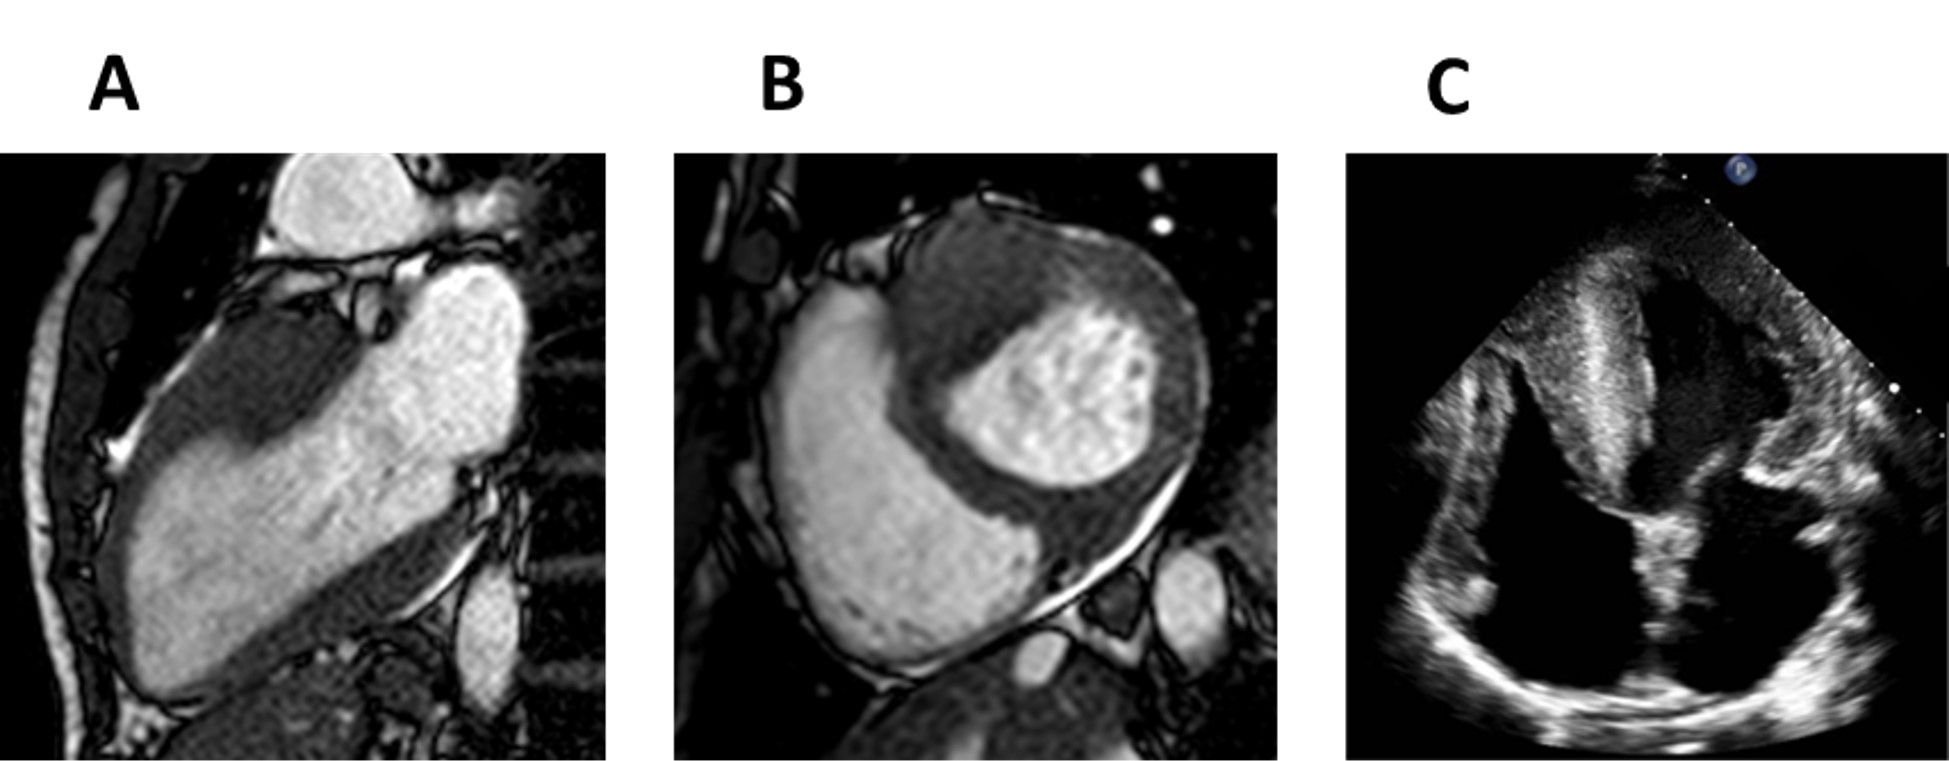

Piecing together all of the previous findings, Nordin et al. [86] was able to construct a three-phase model of cardiac FD progression that subsequently expanded to include a fourth stage based on the findings of Augusto et al. [87]. The proposed phases are as follows: the microvascular, accumulation, inflammation and/or hypertrophy and the fibrosis and/or impairment phase; they are summarized in Table 2 and Figs. 6,7.

Fig. 6.Early stage Fabry disease. (A) Four-chamber cardiac magnetic resonance (CMR) image of a patient with early stage Fabry disease showing no left ventricular hypertrophy. (B) Short-axis late gadolinium enhancement CMR image demonstrating no late gadolinium enhancement. (C) Short-axis CMR T1 colour map demonstrating reduced T1 signal.